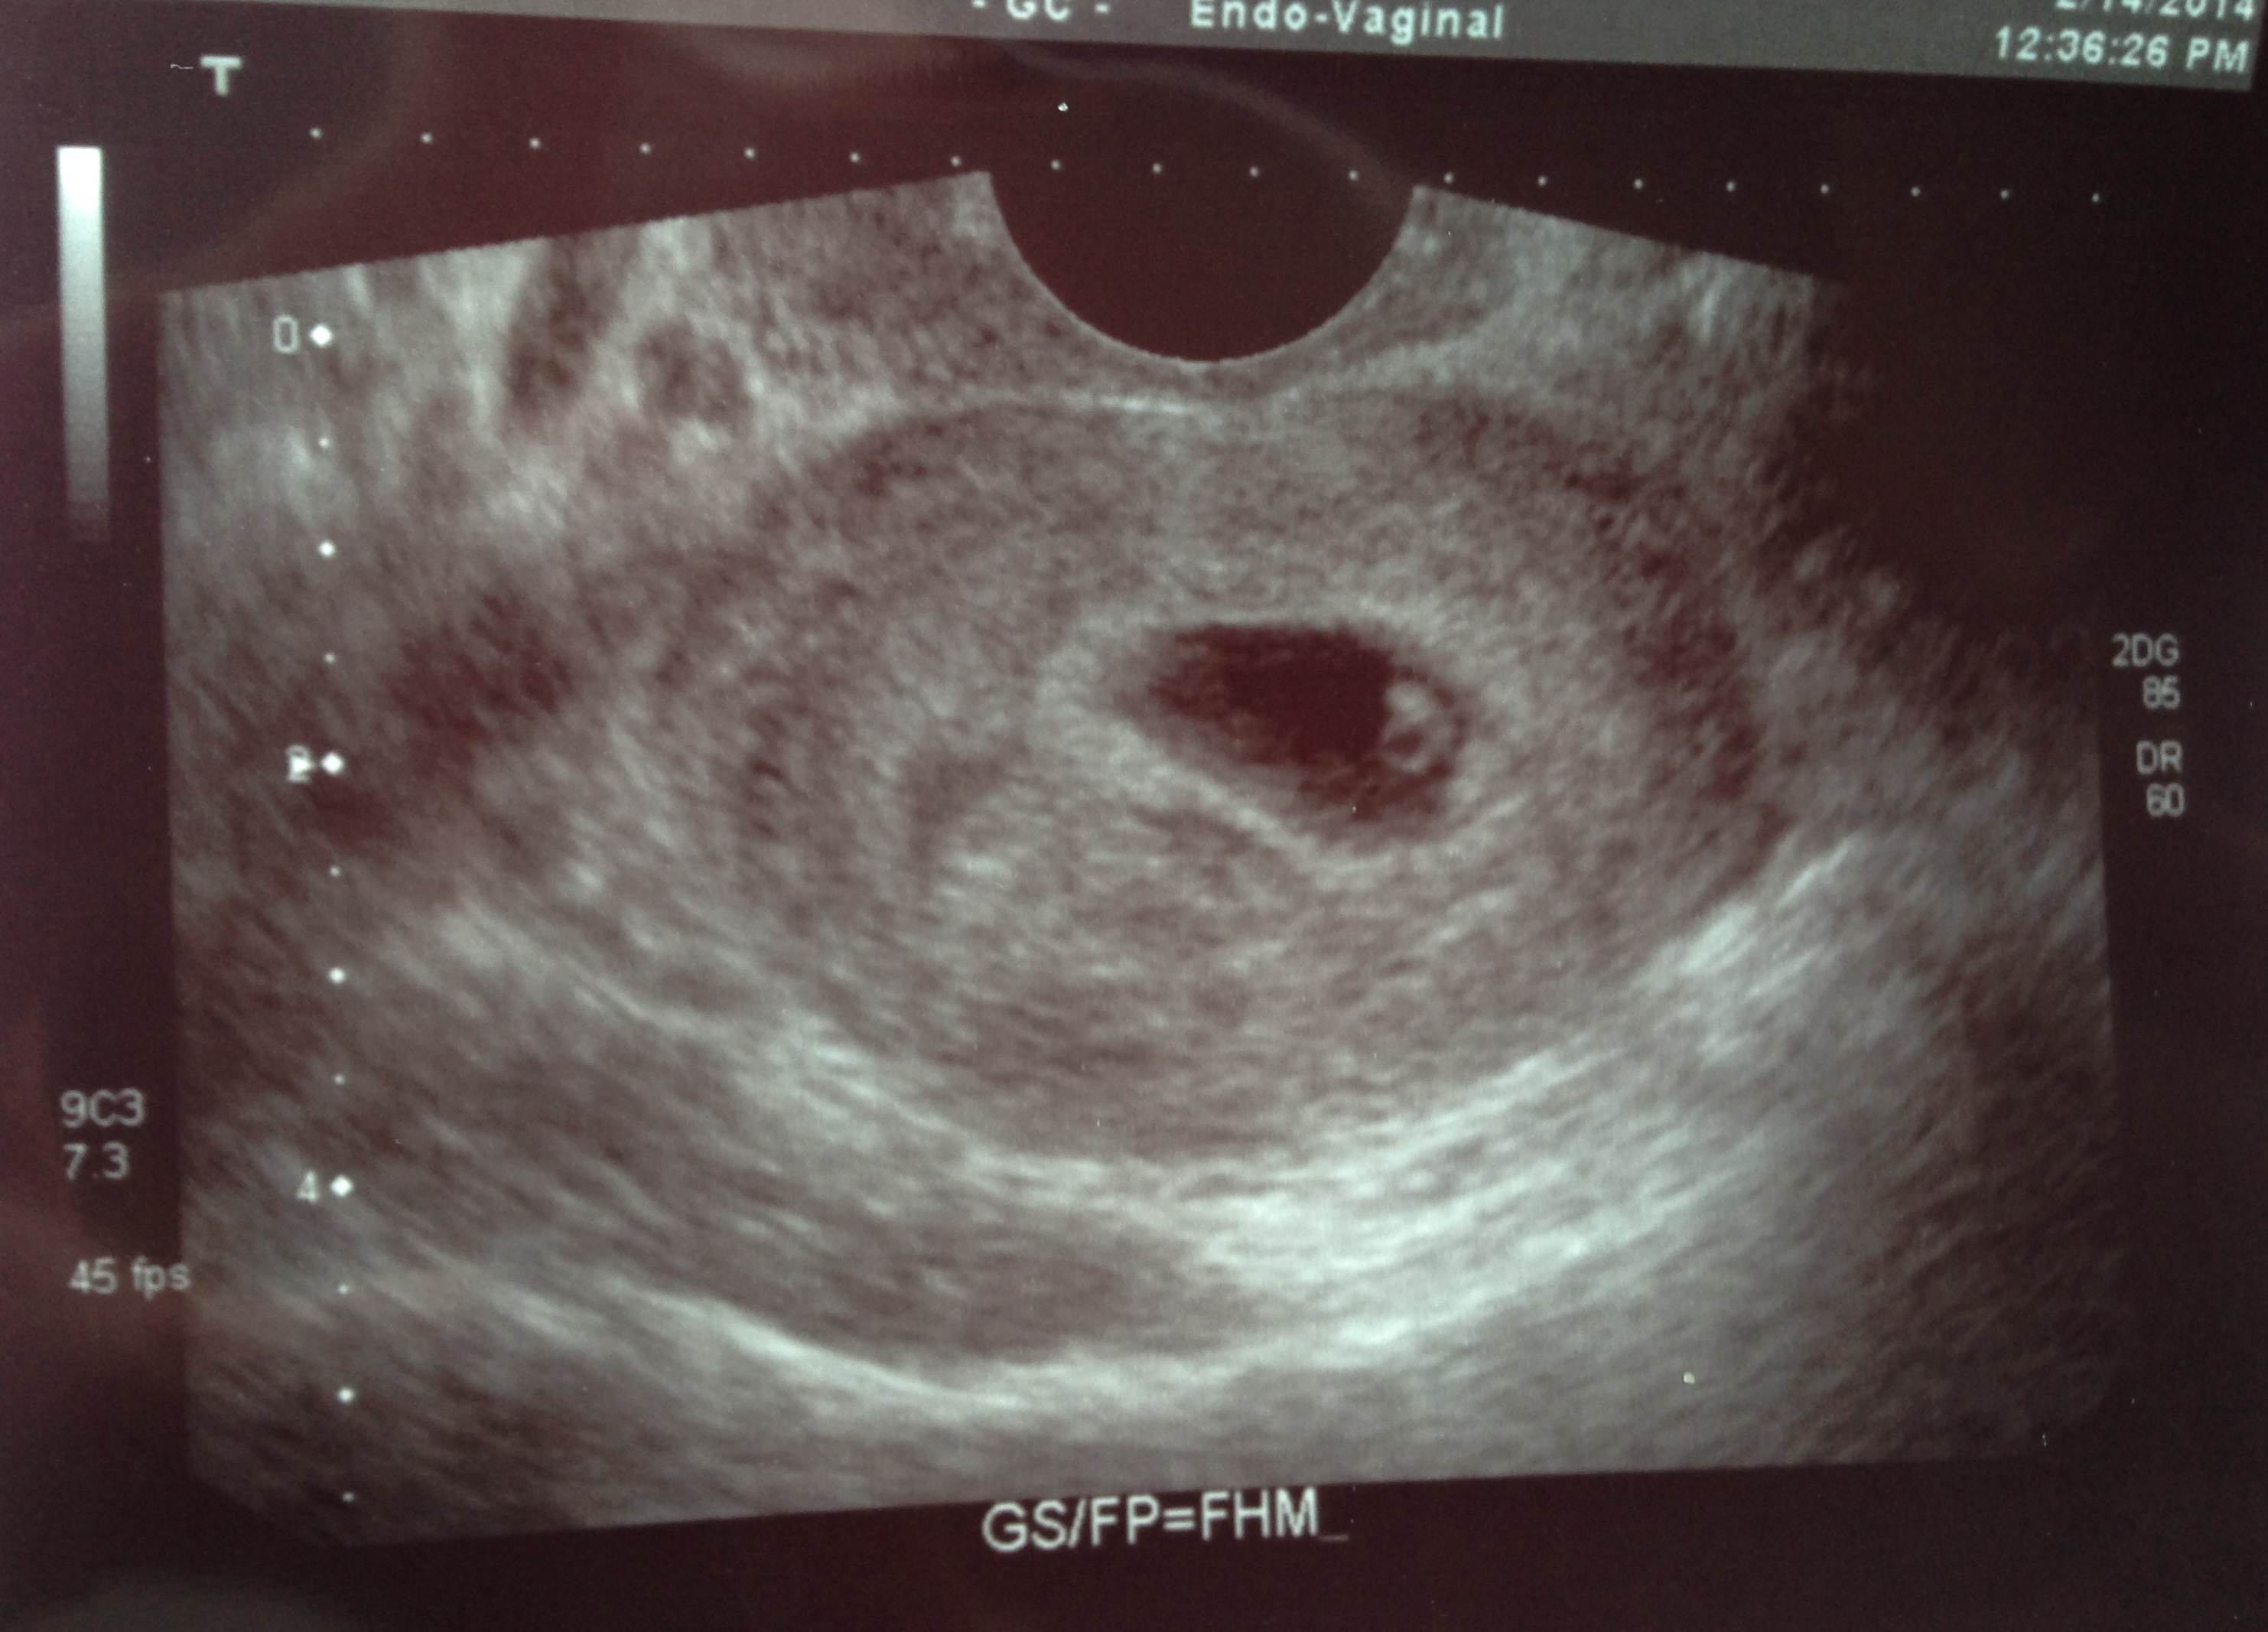

So I don't know that I believe it entirely. But had a girl in my playroom who was really good at it and she explained my first sono with my daughter. It was abdominal and she said it was a great shot for a girl being abdominal. I can't say I really get *how* but she explained the mirror image thing, yada yada. And when I looked at my transvaginal one from my second son, it looked identical (baby and yolk on the same upper left corner). Which made sense because the sono was transvaginal and not abdominal. So...with all that said...this picture being transvaginal, baby is in the opposite positioning as my daughter was on abdominal sono. So I'd guess girl.